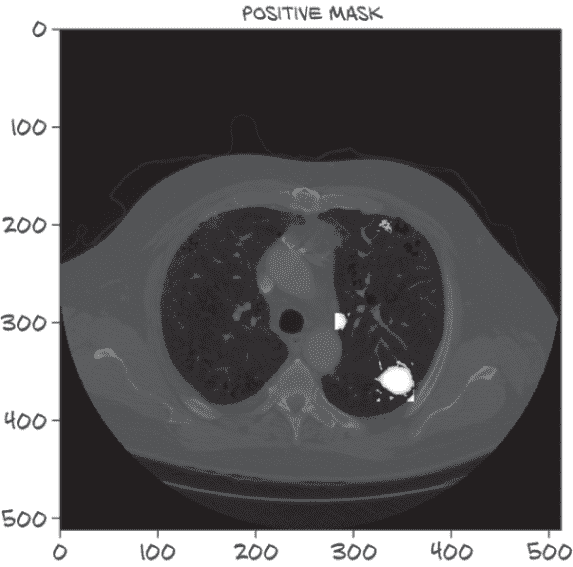

让我们看一下图 13.11,看看这些掩码在实践中是什么样子。完整彩色图像可以在 p2ch13_explore_data.ipynb 笔记本中找到。

图 13.11 ct.positive_mask中突出显示的三个结节,白色标记

右下角的结节掩码展示了我们矩形边界框方法的局限性,包括部分肺壁。这当然是我们可以修复的问题,但由于我们还没有确信这是我们时间和注意力的最佳利用方式,所以我们暂时让它保持原样。接下来,我们将继续将此掩码添加到我们的 CT 类中。